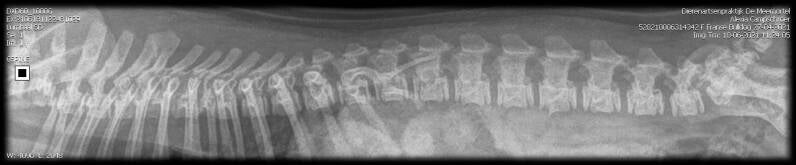

Röntgen foto van de rug,

Ruggenmerg niks gevonden en heeft een goed doorstroming.

Geen spondylose.

Geen verkalkingen over de hele wervelkolom.

Fotoś van Loes, HD, ED, Rug, Heupen.